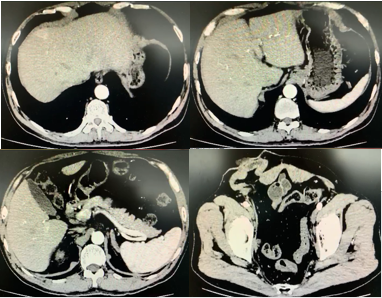

2019-6-18患者复查腹部增强CT:1.肝左叶病灶,转移?2.右输尿管上段病变,炎症?转移性病变?(图6)。2019-8-10复查腹部增强CT:1.肝左叶异常信号灶,请结合MRI增强?2.腹膜后多发小淋巴结,对比2019-6-18大致相仿(图7)。2019年8月16日上腹部MR增强:1.肝右叶S4段占位,倾向囊肿;2.肝左叶异常灌注考虑(图8)。

图6 患者复查腹部增强CT影像资料(2019年6月18日)

图7 患者复查腹部增强CT影像资料(2019年8月10日)